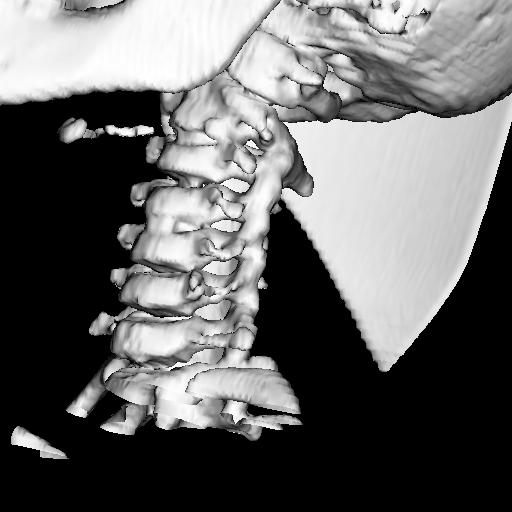

Ребенок 6 лет. Жалобы на выраженные боли в шейном отделе позвоночника. Со слов матери, боли в шее беспокоили длительное время. 2 недели отмечалась незначительная травма - девочка резко повернула голову в сторону, боли в шее услились. В настоящий момент  отмечаются выраженные боли в шее, резкое ограничение движений, повышение температуры тела, воспалительные изменения в анализах, (возможно, связанные с пиелонефритом, который также имеет место). Поступала с направительным диагнозом "ротационный подвывих атланта", однако данные рентгенографии заставили расширить круг диагностического поиска.Родовую травму мать отрицает. Хотелось бы узнать мнение уважаемых коллег.

Уважаемая коллега! С точки зрения классической рентгенологии (с учётом качества представленных снимков) могу высказать следующее:

- определяется выраженный антелистез тела С5;

- двуконтурность тел С3 и С5 может свидетельствовать о нарушении целостности костной ткани указанных тел позвонков;

- безусловно, межпозвонковые диски "поехали".

Вижу ещё раздвоенный axis.

Аксис не раздвоен, это нормальная картина для шести лет, просто верхушка зуба еще хрящевая.

Спасибо. Буду знать. По заданной теме: не хотелось бы быть освистанным, но смею предположить ювенильный ревматоидный артрит.

Случай помню. Закончилось все на удивление просто - после недели вытяжения петлей Глиссона боли ушли, движения в ШОП восстановились в полном объёме. Рентгенологические данные расценили как врожденную аномалию развития. Воспалительные изменения в анализах - как проявления пиелонефрита. В любом случае, из нашего поля зрения ребёнок ушел к нефрологам.